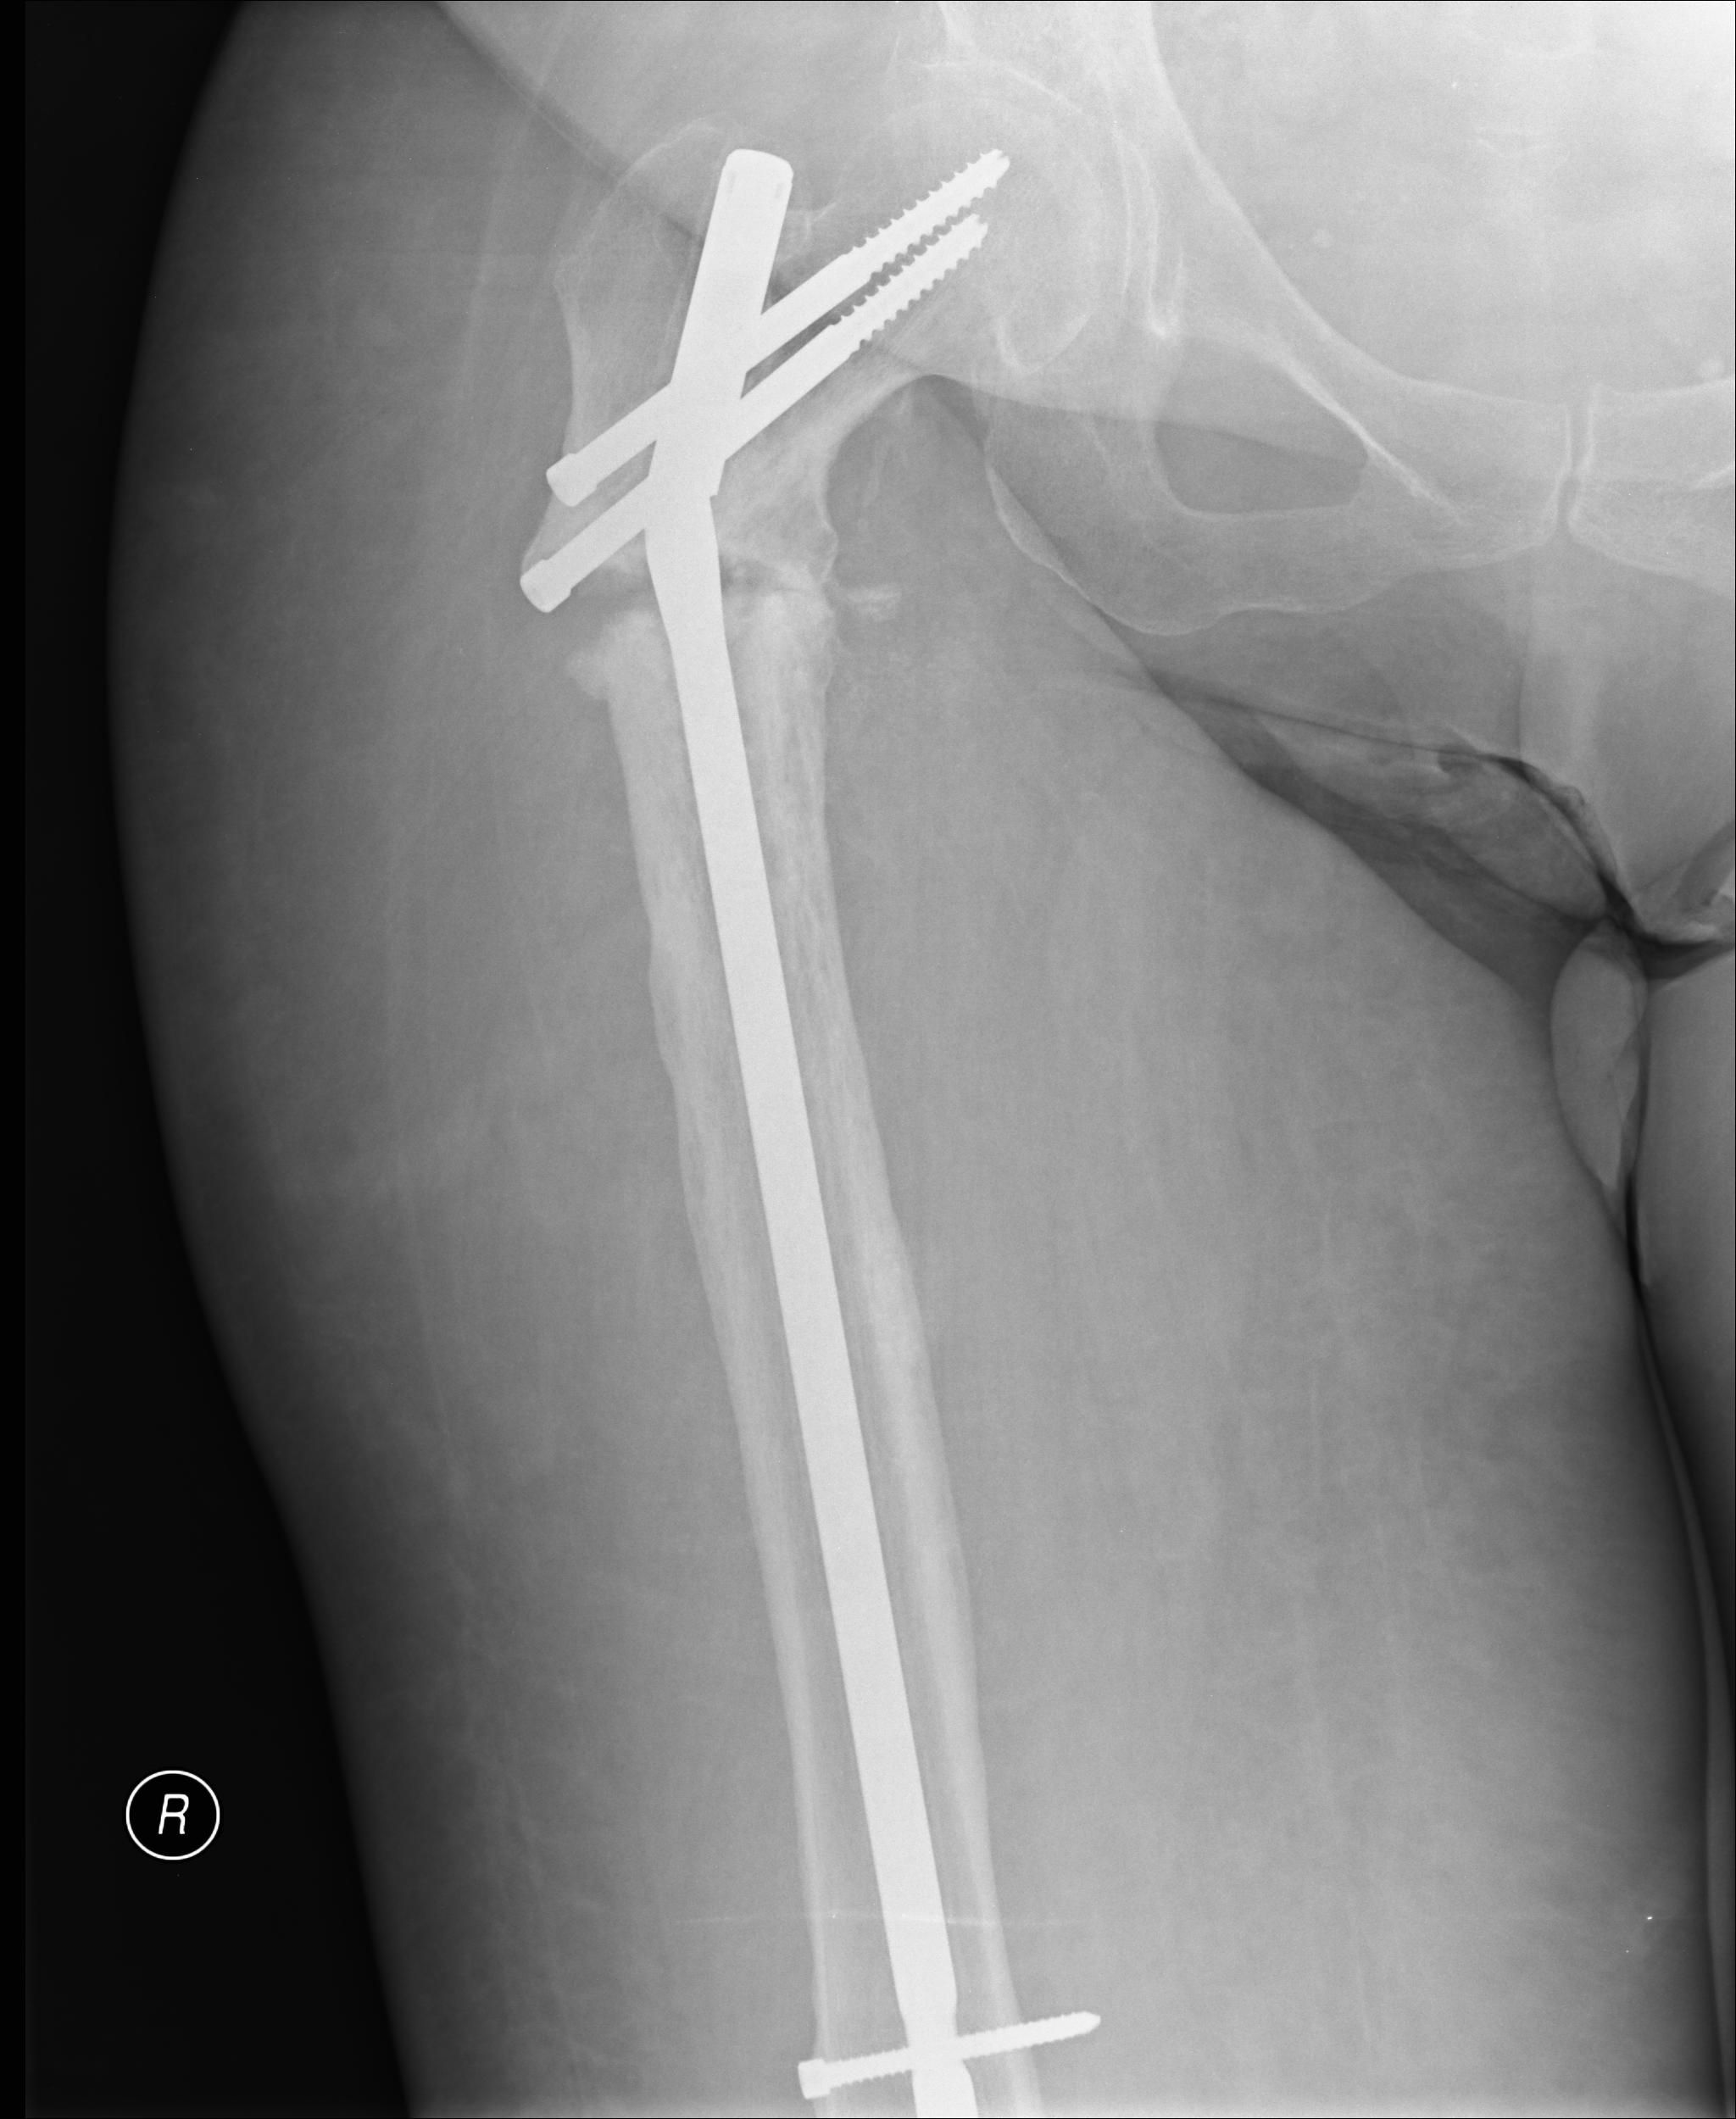

ðÁÔÏÌÏÇÉÞÅÓËÉÊ ÐÏÄ×ÅÒÔÅÌØÎÙÊ ÐÅÒÅÌÏÍ ÂÅÄÒÁ |

âÏÌØÎÁÑ 54 ÇÏÄÁ, 5-6 ÌÅÔ ÎÁÚÁÄ ÚÌÏËÁÞÅÓÔ×ÅÎÎÏÅ ÏÂÒÁÚÏ×ÁÎÉÅ ÐÁÈÏ×ÏÊ ÏÂÌÁÓÔÉ - ÌÕÞÅ×ÁÑ ÔÅÒÁÐÉÑ, ÎÅËÒÏÚ ËÏÓÔÉ. ÐÁÔÏÌÏÇÉÞÅÓËÉÊ ÐÅÒÅÌÏÍ ÂÅÄÒÁ 2 ÇÏÄÁ ÎÁÚÁÄ ÏÓÔÅÏÓÉÎÔÅÚ ÒÅËÏÎÓÔÒÕËÔÉ×ÎÙÍ ÓÔÅÒÖÎÅÍ - ÐÏÌÏÍËÁ ÓÔÅÒÖÎÑ ÞÅÒÅÚ 6 ÍÅÓÑÃÅ×. ðÏÓÌÅÄÎÉÅ ÐÏÌÔÏÒÁ ÇÏÄÁ ÈÏÄÉÔ Ó Ä×ÕÍÑ ËÏÓÔÙÌÑÍÉ É ÓÌÏÍÁÎÎÙÍ ÓÔÅÒÖÎÅÍ. ïËÏÌÏÇÉÞÅÓËÉ ÏÂÓÌÅÄÏ×ÁÎÁ, × ÎÁÓÔÏÑÝÅÅ ×ÒÅÍÑ ÒÅÃÉÄÉ×Ï× ÉÌÉ ÍÅÔÁÓÔÁÚÏ× ÎÅÔ.öÁÌÏÂÙ ÎÁ ÎÅÏÐÏÒÏÓÐÏÓÏÂÎÏÓÔØ ËÏÎÅÞÎÏÓÔÉ.÷ ÐÌÁÎÁÈ ÒÅÏÓÔÅÏÓÉÎÔÅÚ ÇÁÍÍÁ-ÓÔÅÒÖÎÅÍ.õÞÉÔÙ×ÁÑ ÍÁÌÙÊ ÏÐÙÔ ÐÒÉ "ÐÏÓÔÒÁÄÉÁÃÉÏÎÎÙÈ ÐÅÒÅÌÏÍÁÈ" ÉÎÔÅÒÅÓÕÅÔ ÍÎÅÎÉÅ ÓÏÏÂÝÅÓÔ×Á Ï ÃÅÌÅÓÏÏÂÒÁÚÎÏÓÔÉ ÄÅËÏÒÔÉËÁÃÉÉ ÚÏÎÙ ÐÅÒÅÌÏÍÁ É ËÏÓÔÎÏÊ ÐÌÁÓÔÉËÉ ÉÌÉ ÄÏÓÔÁÔÏÞÎÏ "×ÎÕÔÒÅÎÎÅÊ ÐÌÁÓÔÉËÉ" ÏÔ ÒÁÓÓ×ÅÒÌÉ×ÁÎÉÑ ËÁÎÁÌÁ?âÙÔØ ÍÏÖÅÔ ÅÓÔØ É ÄÒÕÇÉÅ ÓÐÏÓÏÂÙ ÁËÔÉ×ÁÃÉÉ ÓÒÁÝÅÎÉÑ?óÐÁÓÉÂÏ,á.óÉÔÎÉË

ë ÓÏÖÁÌÅÎÉÀ, ÜÔÏÔ ÐÅÒÅÌÏÍ ÎÅ ÓÒÁÓÔ£ÔÓÑ. ëÏÓÔØ ÍÅÒÔ×Á ÐÏÓÌÅ ÒÁÄÉÁÃÉÉ. ëÏÓÔÎÁÑ ÐÌÁÓÔÉËÁ ÔÏÖÅ ÎÅ ÐÏÍÏÖÅÔ. ÷ÁÍ ÎÁÄÏ ÄÅÌÁÔØ ÚÁÍÅÎÕ ÐÒÏËÓÉÍÁÌØÎÏÊ ÞÁÓÔÉ ÂÅÄÒÁ (proximal femoral replacement). ðÁÃÉÅÎÔËÁ ×ÓÔÁÎÅÔ ÎÁ ÎÏÇÉ Ó ÐÏÌÎÏÊ ÏÐÏÒÏÊ ÓÒÁÚÕ ÐÏÓÌÅ ÏÐÅÒÁÃÉÉ. üÔÏ ÎÁÉÂÏÌÅÅ ÎÁÄ£ÖÎÙÊ ×ÁÒÉÁÎÔ.